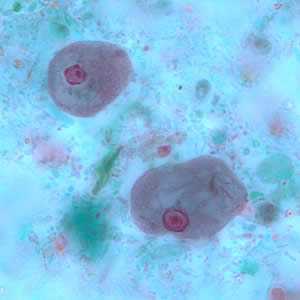

E. nana trophozoites stained with trichrome.

Figure A: Trophozoite of E. nana stained with trichrome.

Figure B: Trophozoites of E. nana stained with trichrome.

Figure C: Trophozoite of E. nana stained with trichrome.

Figure D: Trophozoite of E. nana stained with trichrome. Image courtesy of the Kansas Department of Health and Environment.

Figure E: Trophozoite of E. nana stained with trichrome.